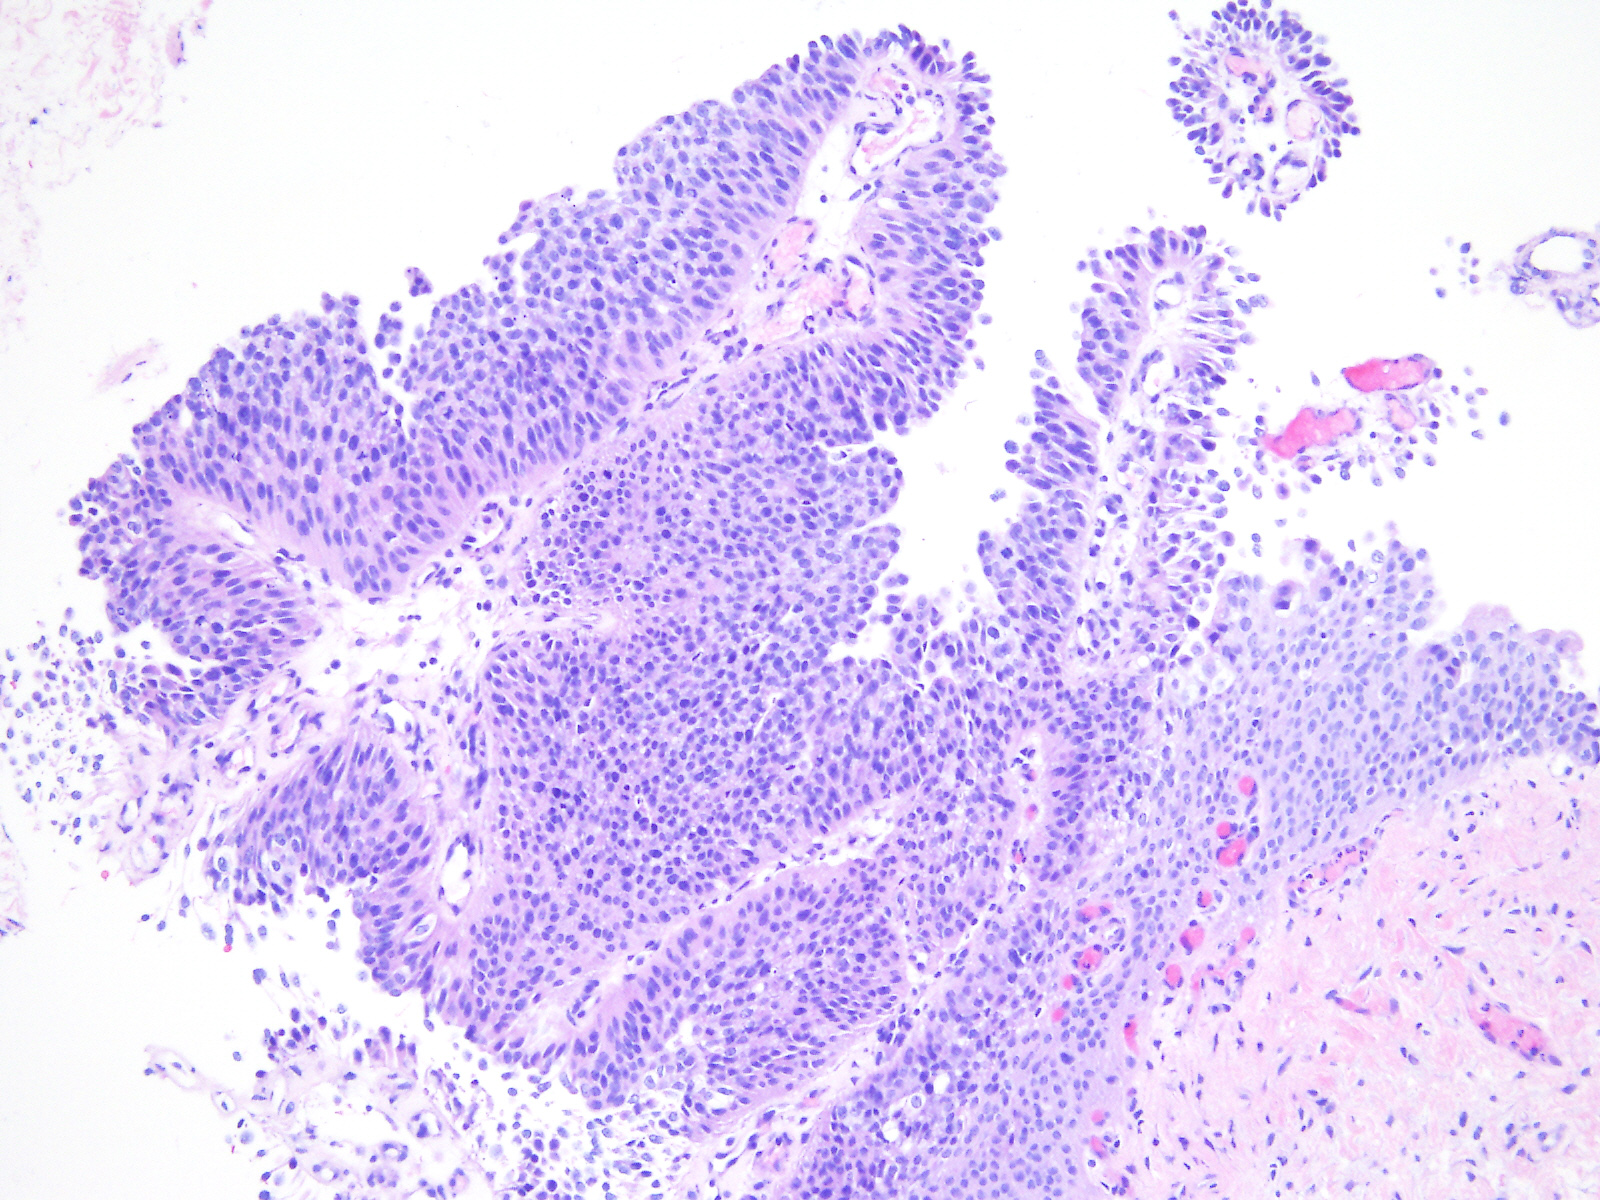

Bladder Papillary Lesions

Case ID: 543